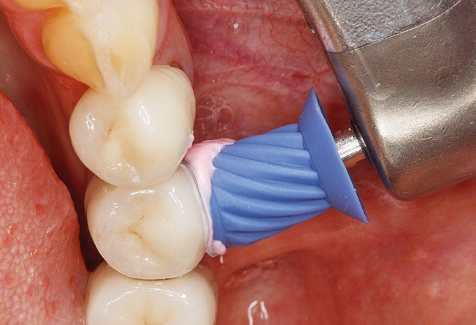

Good illumination of the working field facilitates the process considerably. The system used by the authors achieves this thanks to a 5x LED ring integrated in the handpiece. Naturally, a range of working tips for different indications is also offered. A straight, universally employable tip is the basic instrument required for machine cleaning of natural teeth (Fig. 5a and b). Curved tips, which allow access to exposed furcations, are also available for hard-to-reach areas in the posterior region (Fig. 6).

Of course, working tips for the cleaning of implant surfaces are also indispensable for SPT in patients fitted with implants. The implant cleaning attachment on the system used here is characterised by its tapered, hexagonal design. This design allows light, atraumatic penetration of the peri-implant pocket and displays a good cleaning performance (Fig. 7).